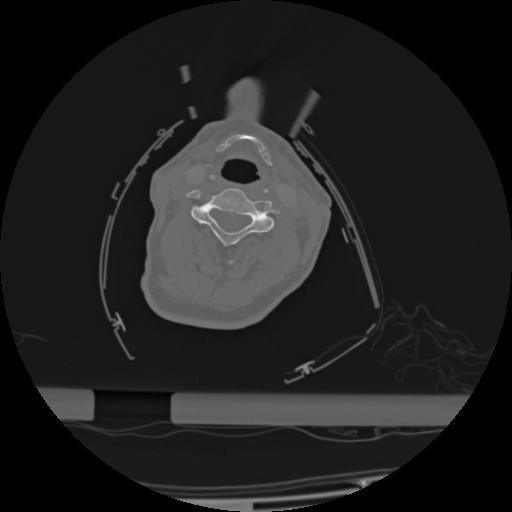

22 ANGIO,CE,Vol,0.5,ANGIO,,